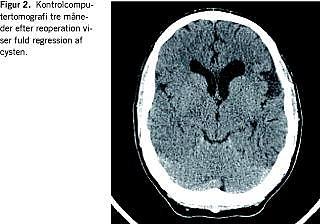

Akut computertomografi viste et venstresidigt subduralt let hyperdenst hæmatom kombineret med en 6 cm stor venstresidig temporofrontal arachnoideacyste, som indeholdt blod. Der var subfalcin herniering på 10 mm (Figur 1 ).

Samtidigt med at der blev tilkaldt en neurokirurg, blev patienten bevidstløs med ekstensionsspasmer i ekstremiteterne. Han blev umiddelbart intuberet og hyperventileret, og der blev givet mannitol intravenøst (1 g/kg). Ved den efterfølgende operation blev der via en venstresidig kraniotomi udtømt et flydende subduralt hæmatom samt indholdet (også flydende blod) af cysten.